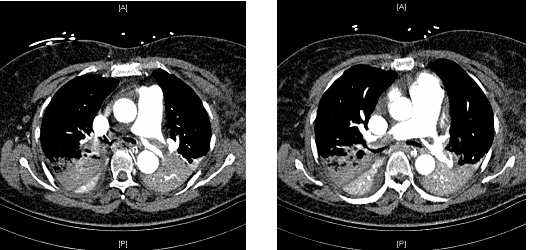

She was brought to the emergency department, where vital signs were notable for temperature of 100.9ºF, HR=142/min, BP=90/60 mmHg after intravenous fluids, with oxygen saturation of 99% while breathing 100% oxygen via non-rebreather mask. Computed tomography of the chest with pulmonary angiogram protocol (Figure 1) revealed large, thrombi in the right main and left main pulmonary arteries with incomplete occlusion, in addition to multiple segmental thrombi in right upper, middle and lower lobes. No lower extremity deep vein thromboses were noted on venogram. Anticoagulation was initiated and the patient was transferred to the intensive care unit (ICU) for further management.

FIGURE 1: CT scan of the chest demonstrating pulmonary emboli in bilateral main pulmonary artery